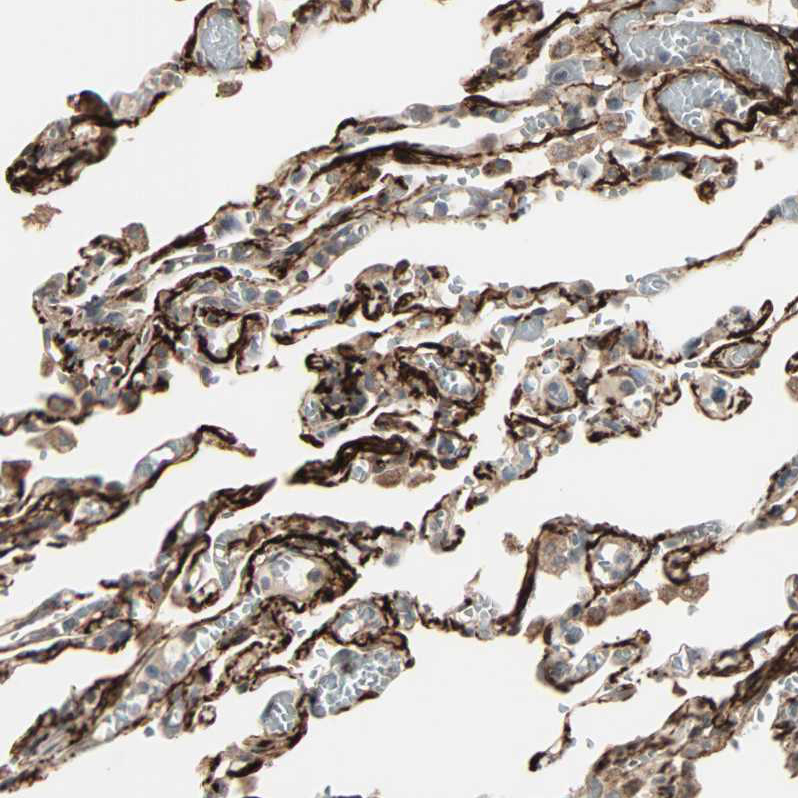

Immunohistochemical staining of human Lung shows strong membranous positivity in pneumocytes.